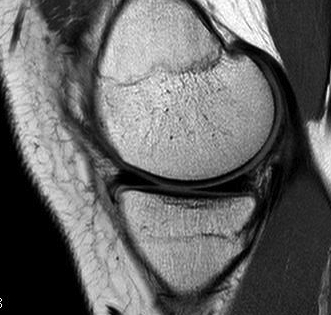

MRI Classification

Stoller 1987 J. Radiol.

Grade 0

- normal homogeneous low signal intensity

Grade I

- globular increase signal in meniscus

- doesn't reach either surface

Grade II

- linear increase signal, doesn't reach surface

- myxoid intra-meniscal degeneration / partially healed tear

Grade III

- increased signal intensity communicates with meniscal surface

- 70-90% accurate for true tear

- accuracy MM > LM

Signs of bucket handle tear meniscus

1. Double PCL sign

- medial Meniscus

2. Absent bow tie sign

- should see bow tie image on 2 consecutive sagittal slices of 5 mm

3. Fragment in notch sign

4. Anterior flipped meniscal sign

- torn fragment flips over the anterior horn of the affected meniscus

5. Truncated meniscus